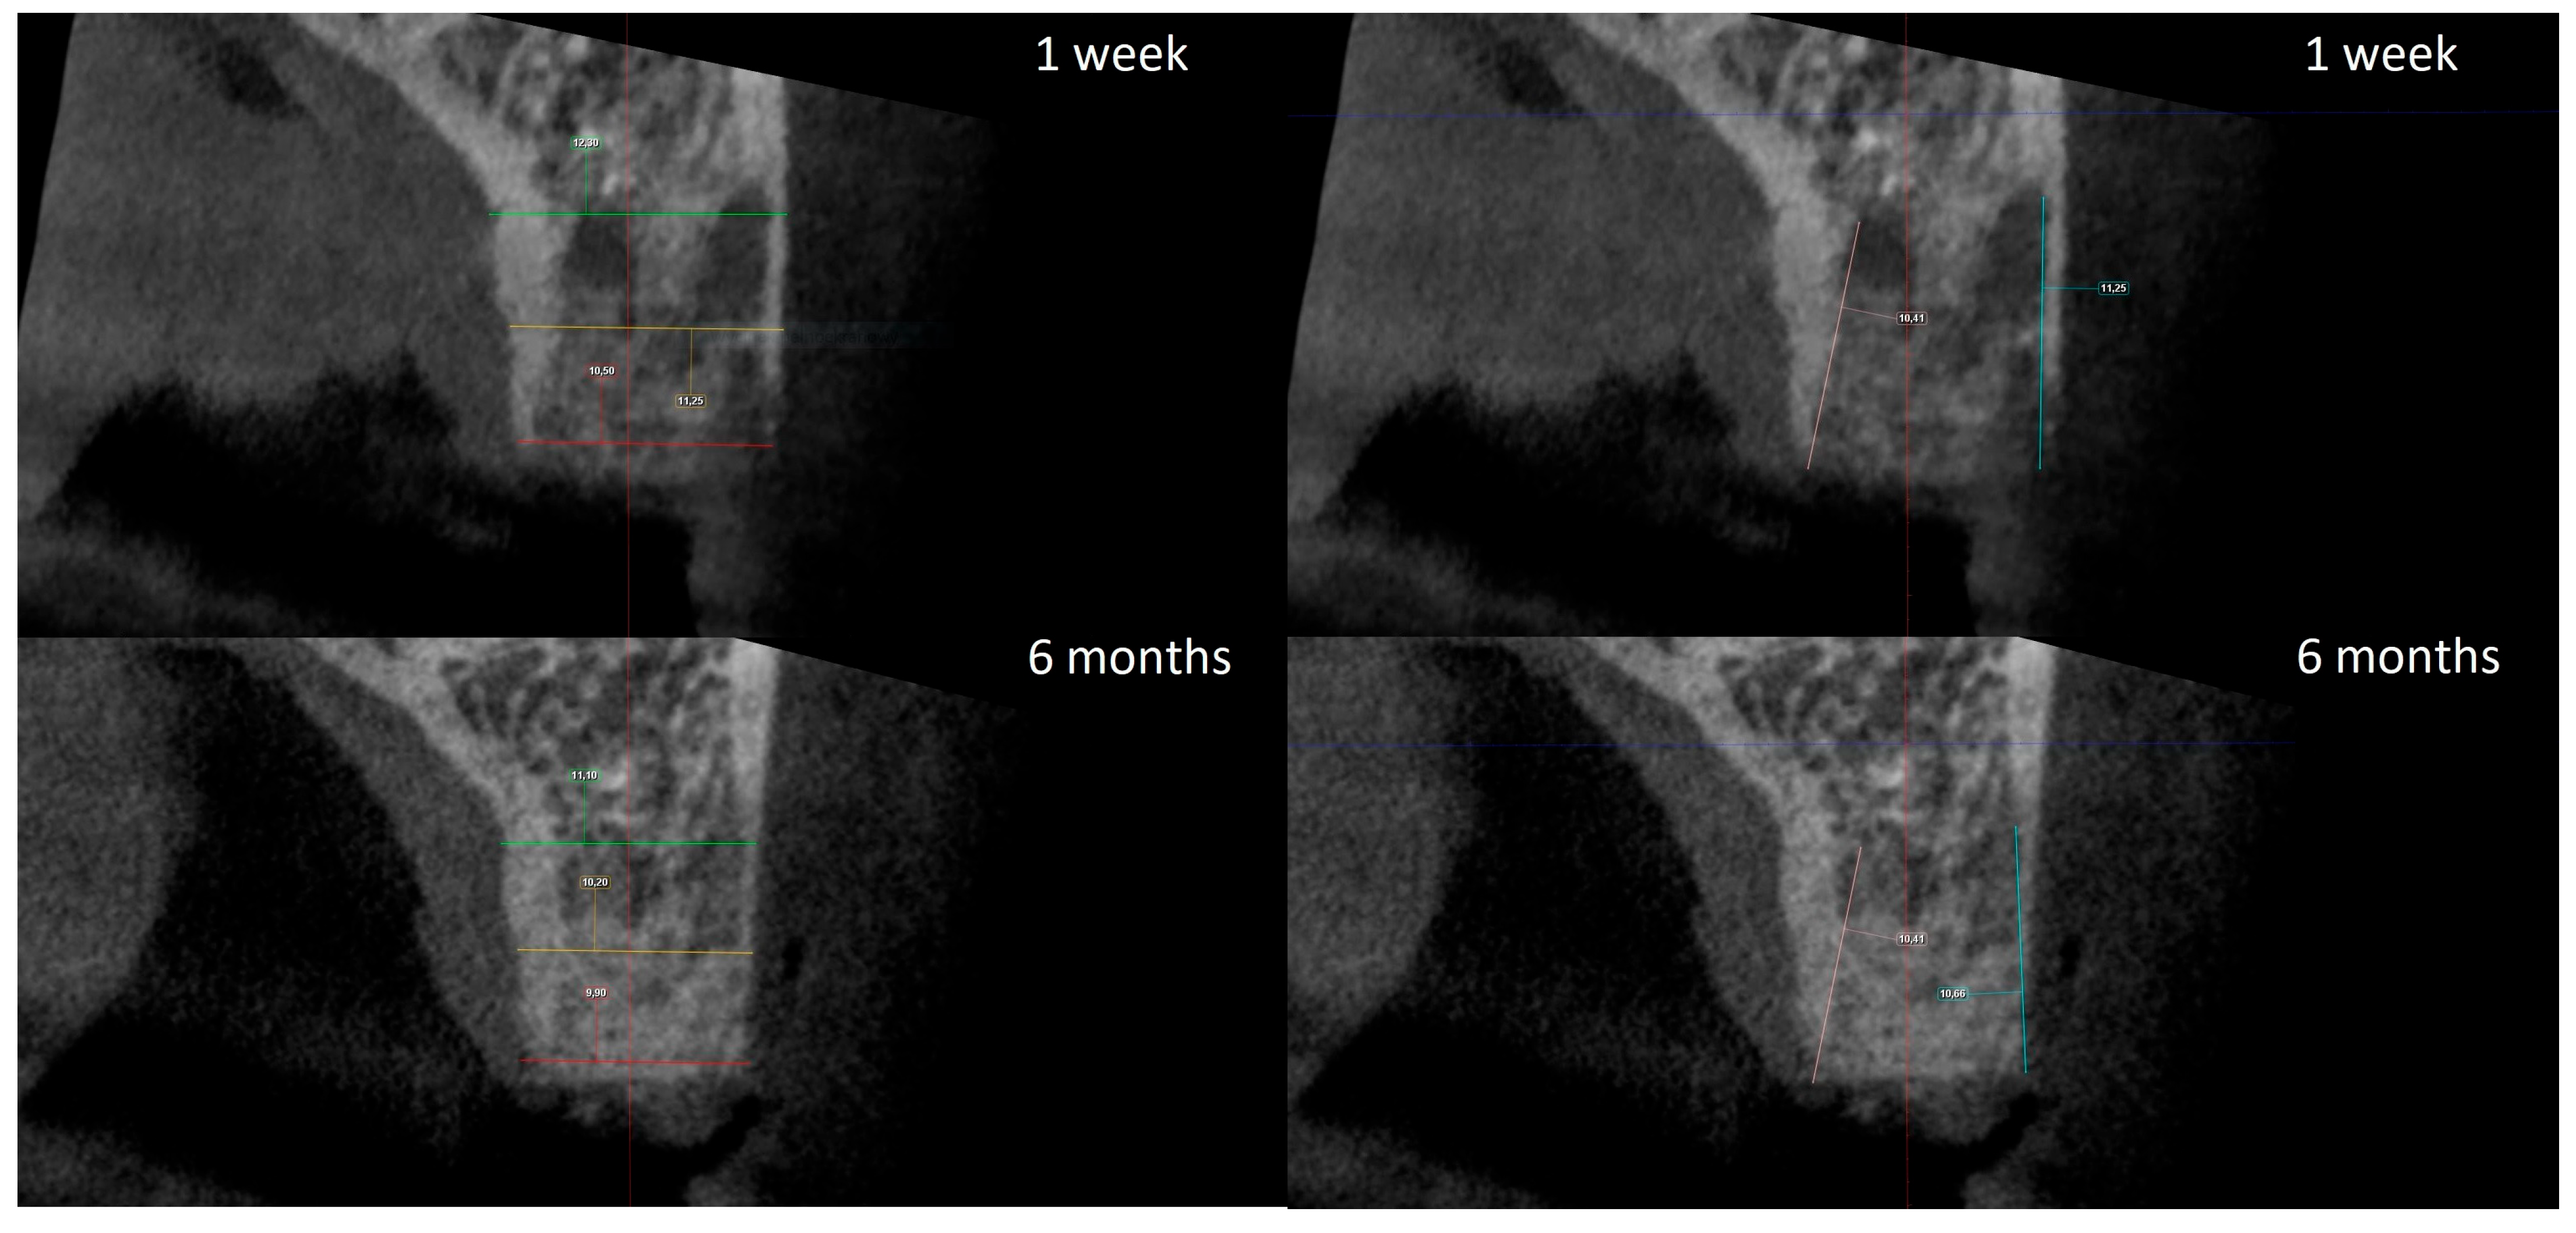

The radiographic analysis consisted of alveolar ridge dimension measurements taken 1 week and 6 months post socket preservation surgery. The measurements were made using the Romexis software provided by the Planmeca company. The superimposition of the radiographic images was created automatically by selecting 3 reference points, most often the incisal edges and cusps of adjacent teeth. Afterward, the images were manually corrected (Figure 3). The above-mentioned steps ensured the repeatability of the measurements carried out on sagittal planes, which were oriented in such a manner that the buccal bone plate was parallel to the long axis. The measurements were made in the central part of the alveolus. The distance between the buccal and palatal bony plates was measured at the alveolar crest, the bottom of the alveolus, and midway between these two points (Figure 4A). The height was measured from the bottom of the alveolus to the top of the buccal and palatal bony plates, respectively (Figure 4B).

Figure 4.

(A) Alveolar ridge width measurements: coronally (red line), midpoint (yellow line) and apically (green line); (B) alveolar ridge height measurements: buccally (blue line) and palatally (pink line).

The width and height measurements taken seven days and six months after surgery allowed for the calculation of the alterations of the given dimensions over the healing period. The obtained data are presented in Table 1.

Table 1.

Comparison of alveolar ridge width and height alterations, in millimeters, after 6 months of healing.

The statistical analysis demonstrated no statistically significant differences between groups for all parameters except buccal height alteration. The latter was significantly higher in the xenograft group, with a 1.3 mm average, compared to the 0.5 mm average in the allograft group. For this particular comparison, the statistical significance was estimated to be p = 0.01.

3.2. Optical Bone Density Measurement

The optical density measurements were performed on 10 consecutive cross-sections selected from the central portion of the alveolus in each patient. The measurements were made for representative regions of interest (ROIs) in the augmented site. The data obtained are presented in Table 2.

Table 2.

Mean optical bone density levels in Hounsfield units.

It is worth noting that in the allograft group, the mean optical density increased from 1341.40 to 1499.94 HU. However, the difference was statistically insignificant; therefore, one may only conclude that there was a growth tendency. In contrast, in the xenograft group, the mean optical density increased from 1288.58 to 1881.08 HU, which was statistically significant at p = 0.004.